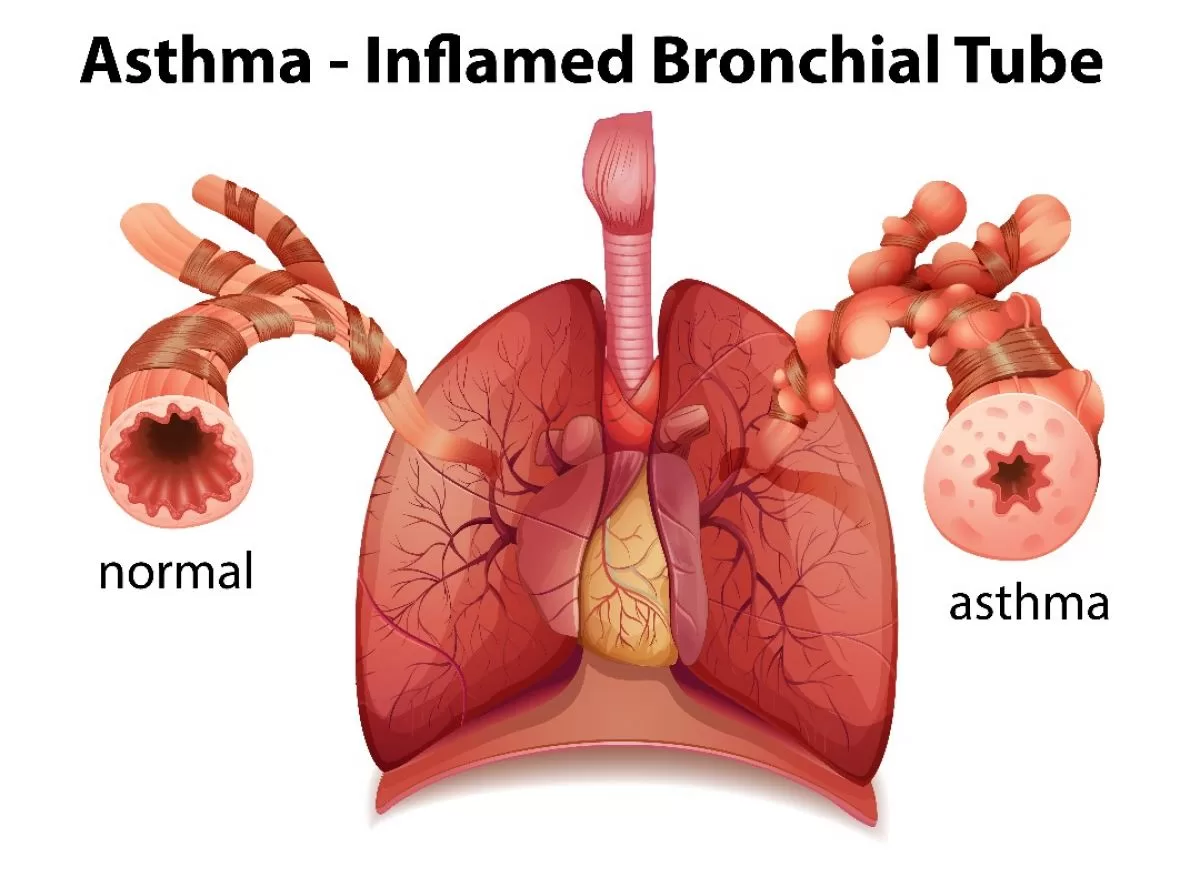

1. Asma

Asma adalah gangguan pada saluran pernapasan yang diakibatkan oleh kontraksi otot polos pada trakea dan mengakibatkan penderita sulit bernapas ditandai dengan kontraksi yang kaku dari bronkiolus.

Asma biasanya disebabkan oleh hipersensitivas bronkiolus terhadap benda-benda asing di udara. Penyebab penyakit ini juga dapat terjadi dikarenakan faktor psikis dan penyakit menurun.